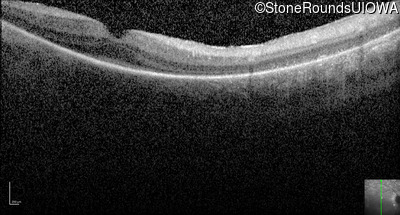

Optical Coherence Tomography - Right -

No Light Perception

Exemplar

Expanded OCT Stack

×